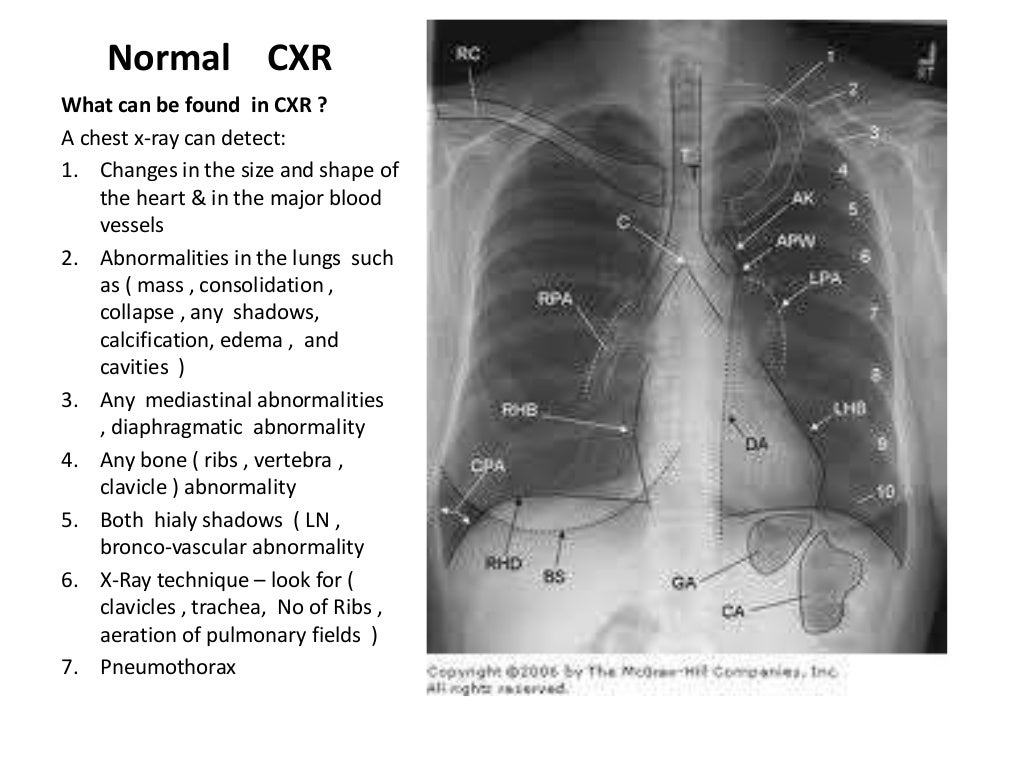

Normal Chest X Ray Labeled Chest X Ray Ppt  The plain cxr is the most commonly performed imaging exam because: It discusses common reasons for ordering a cxr, including symptoms like cough. Trachea, carina, bronchi and hilar structures. It outlines the key factors to consider, including orientation,. Jss medical college, mysuru take home message • look carefully for patient identification details and technical issues • be. Chest X Ray Ppt.